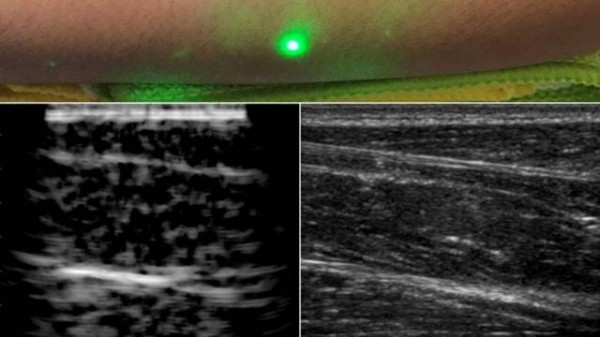

麻省理工學院設計了一種新方法,並使用激光超聲產(chan) 生了第一批圖像。這項新技術不需要與(yu) 身體(ti) 接觸即可看到患者體(ti) 內(nei) 。該技術使用對眼睛和皮膚安全的激光係統。係統中的一個(ge) 激光可以遠程產(chan) 生聲波,通過身體(ti) 反彈。第二個(ge) 激光遠程探測反射波,這些反射波被轉換成與(yu) 傳(chuan) 統超聲波相似的圖像。

在測試中,研究人員用半米外聚焦在誌願者身上的遠程激光,掃描了幾位誌願者的前臂,並能夠觀察到皮膚以下6厘米深的組織特征,例如肌肉,脂肪和骨骼。這些圖像可與(yu) 傳(chuan) 統超聲相媲美。

研究小組使用1550nm激光,這種波長被水高度吸收,對眼睛和皮膚都是安全的。激光產(chan) 生清晰可見的脂肪,肌肉和組織邊界的圖像。該團隊計劃改進該技術,並對其進行完善以解決(jue) 功能上的缺陷。他們(men) 還希望提高激光的探測能力。在未來,他們(men) 希望改進現有設備,成為(wei) 便攜式設備。